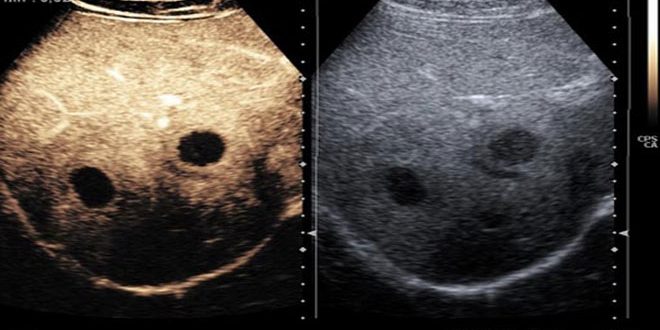

ويفضل ماضي في تصريح لنشرة سانا الصحية تشخيص أورام الكبد بتقنية الايكو ظليل لكونها اجراء بسيطا وسهلا لا يتطلب سوى ست دقائق ويجنب

المريض التعرض لمخاطر الأشعة في حالة التصوير الطبقي المحوري والرنين المغناطيسي.